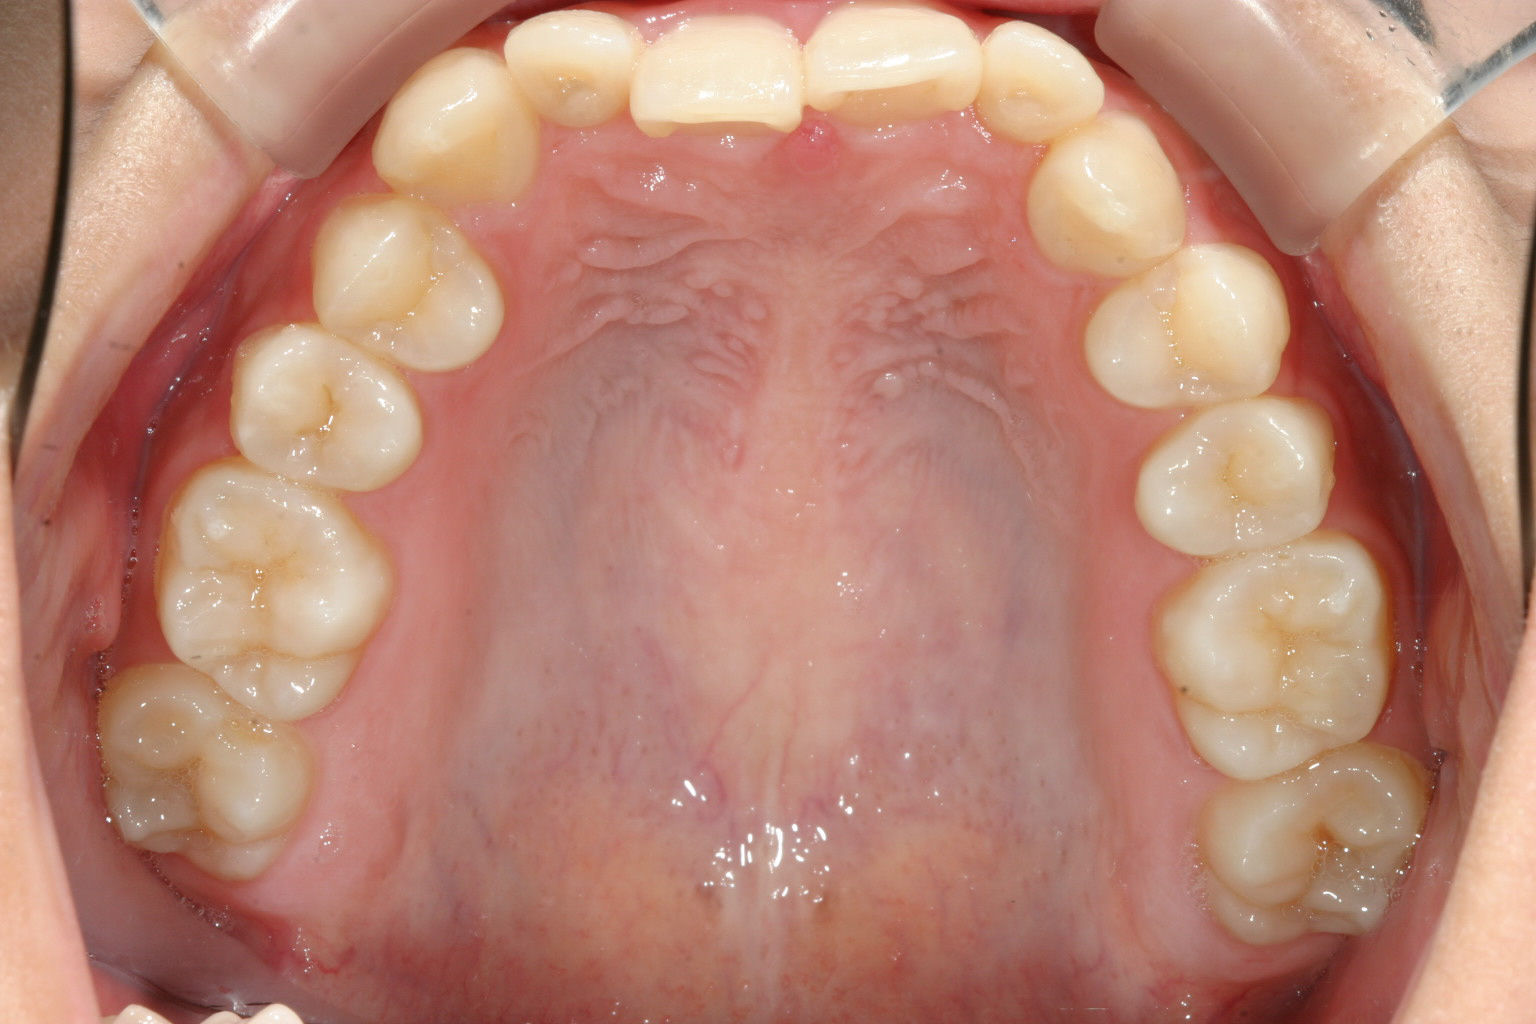

上の前歯が中に入っている為、下あごが前に出ずらく顎関節症をおこし易い咬み合わせです。

上の前歯に押されたせいで下の前歯がガタガタになっています。

かなりのオーバーバイトです。

上の歯並びを綺麗なアーチにする為に前歯を出しました。